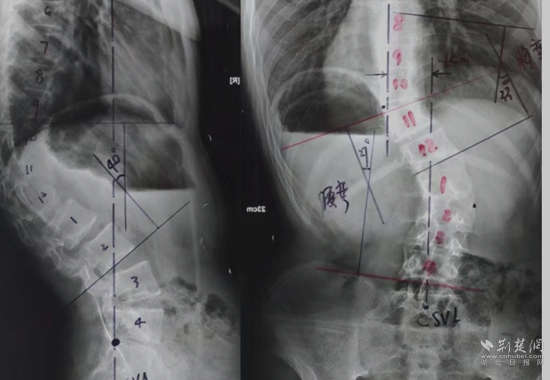

全脊柱X光檢查。通訊員 供圖

余國慶醫(yī)生檢查后發(fā)現(xiàn),這名患者全身皮膚長滿咖啡色的斑塊和瘤狀的突起,身體極為消瘦,骨架突出后可以看到明顯的駝背、剃刀背及側(cè)彎畸形。結(jié)合隨后的全脊柱X光檢查,確診這是一例少見的神經(jīng)纖維瘤病性脊柱側(cè)后凸畸形患者。余醫(yī)生當即將這名患者收住院治療。